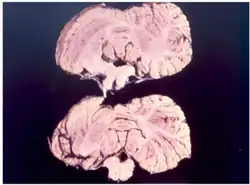

Куру — это трансмиссивная губчатая энцефалопатия, является заболеванием нервной системы, которое вызывает физиологические и неврологические последствия, которые в конечном итоге приводят к смерти. Характеризуется прогрессирующей мозжечковой атаксией или потерей координации и контроля над мышечными движениями[12][13].

Патогенез